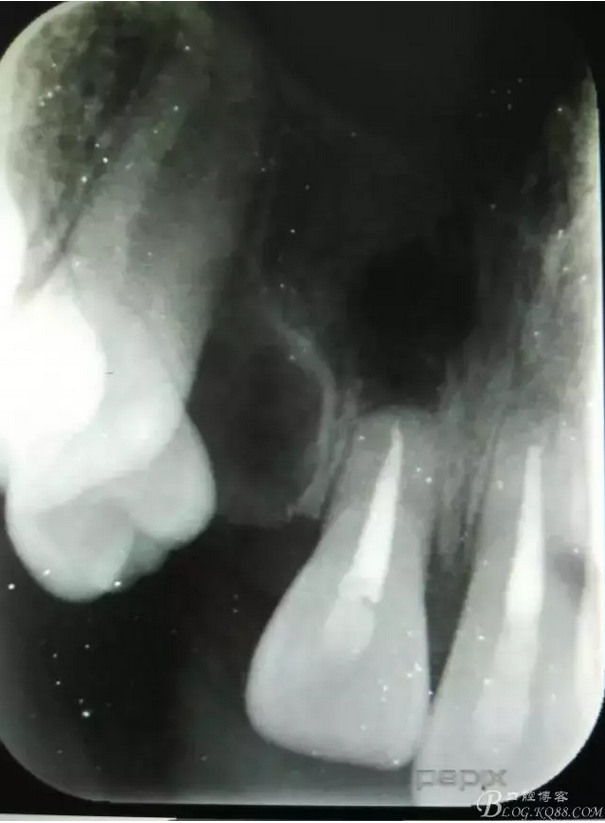

患者、李xx、男、15歲,主訴:牙不齊,矯正牙齒。??茩z查:發(fā)現(xiàn)11、21根尖三分之一折斷,患者否認(rèn)有外傷史。正畸科治療建議如圖1.。術(shù)前簽手術(shù)同意書。

圖1.患者術(shù)前的正畸科檢查病歷: